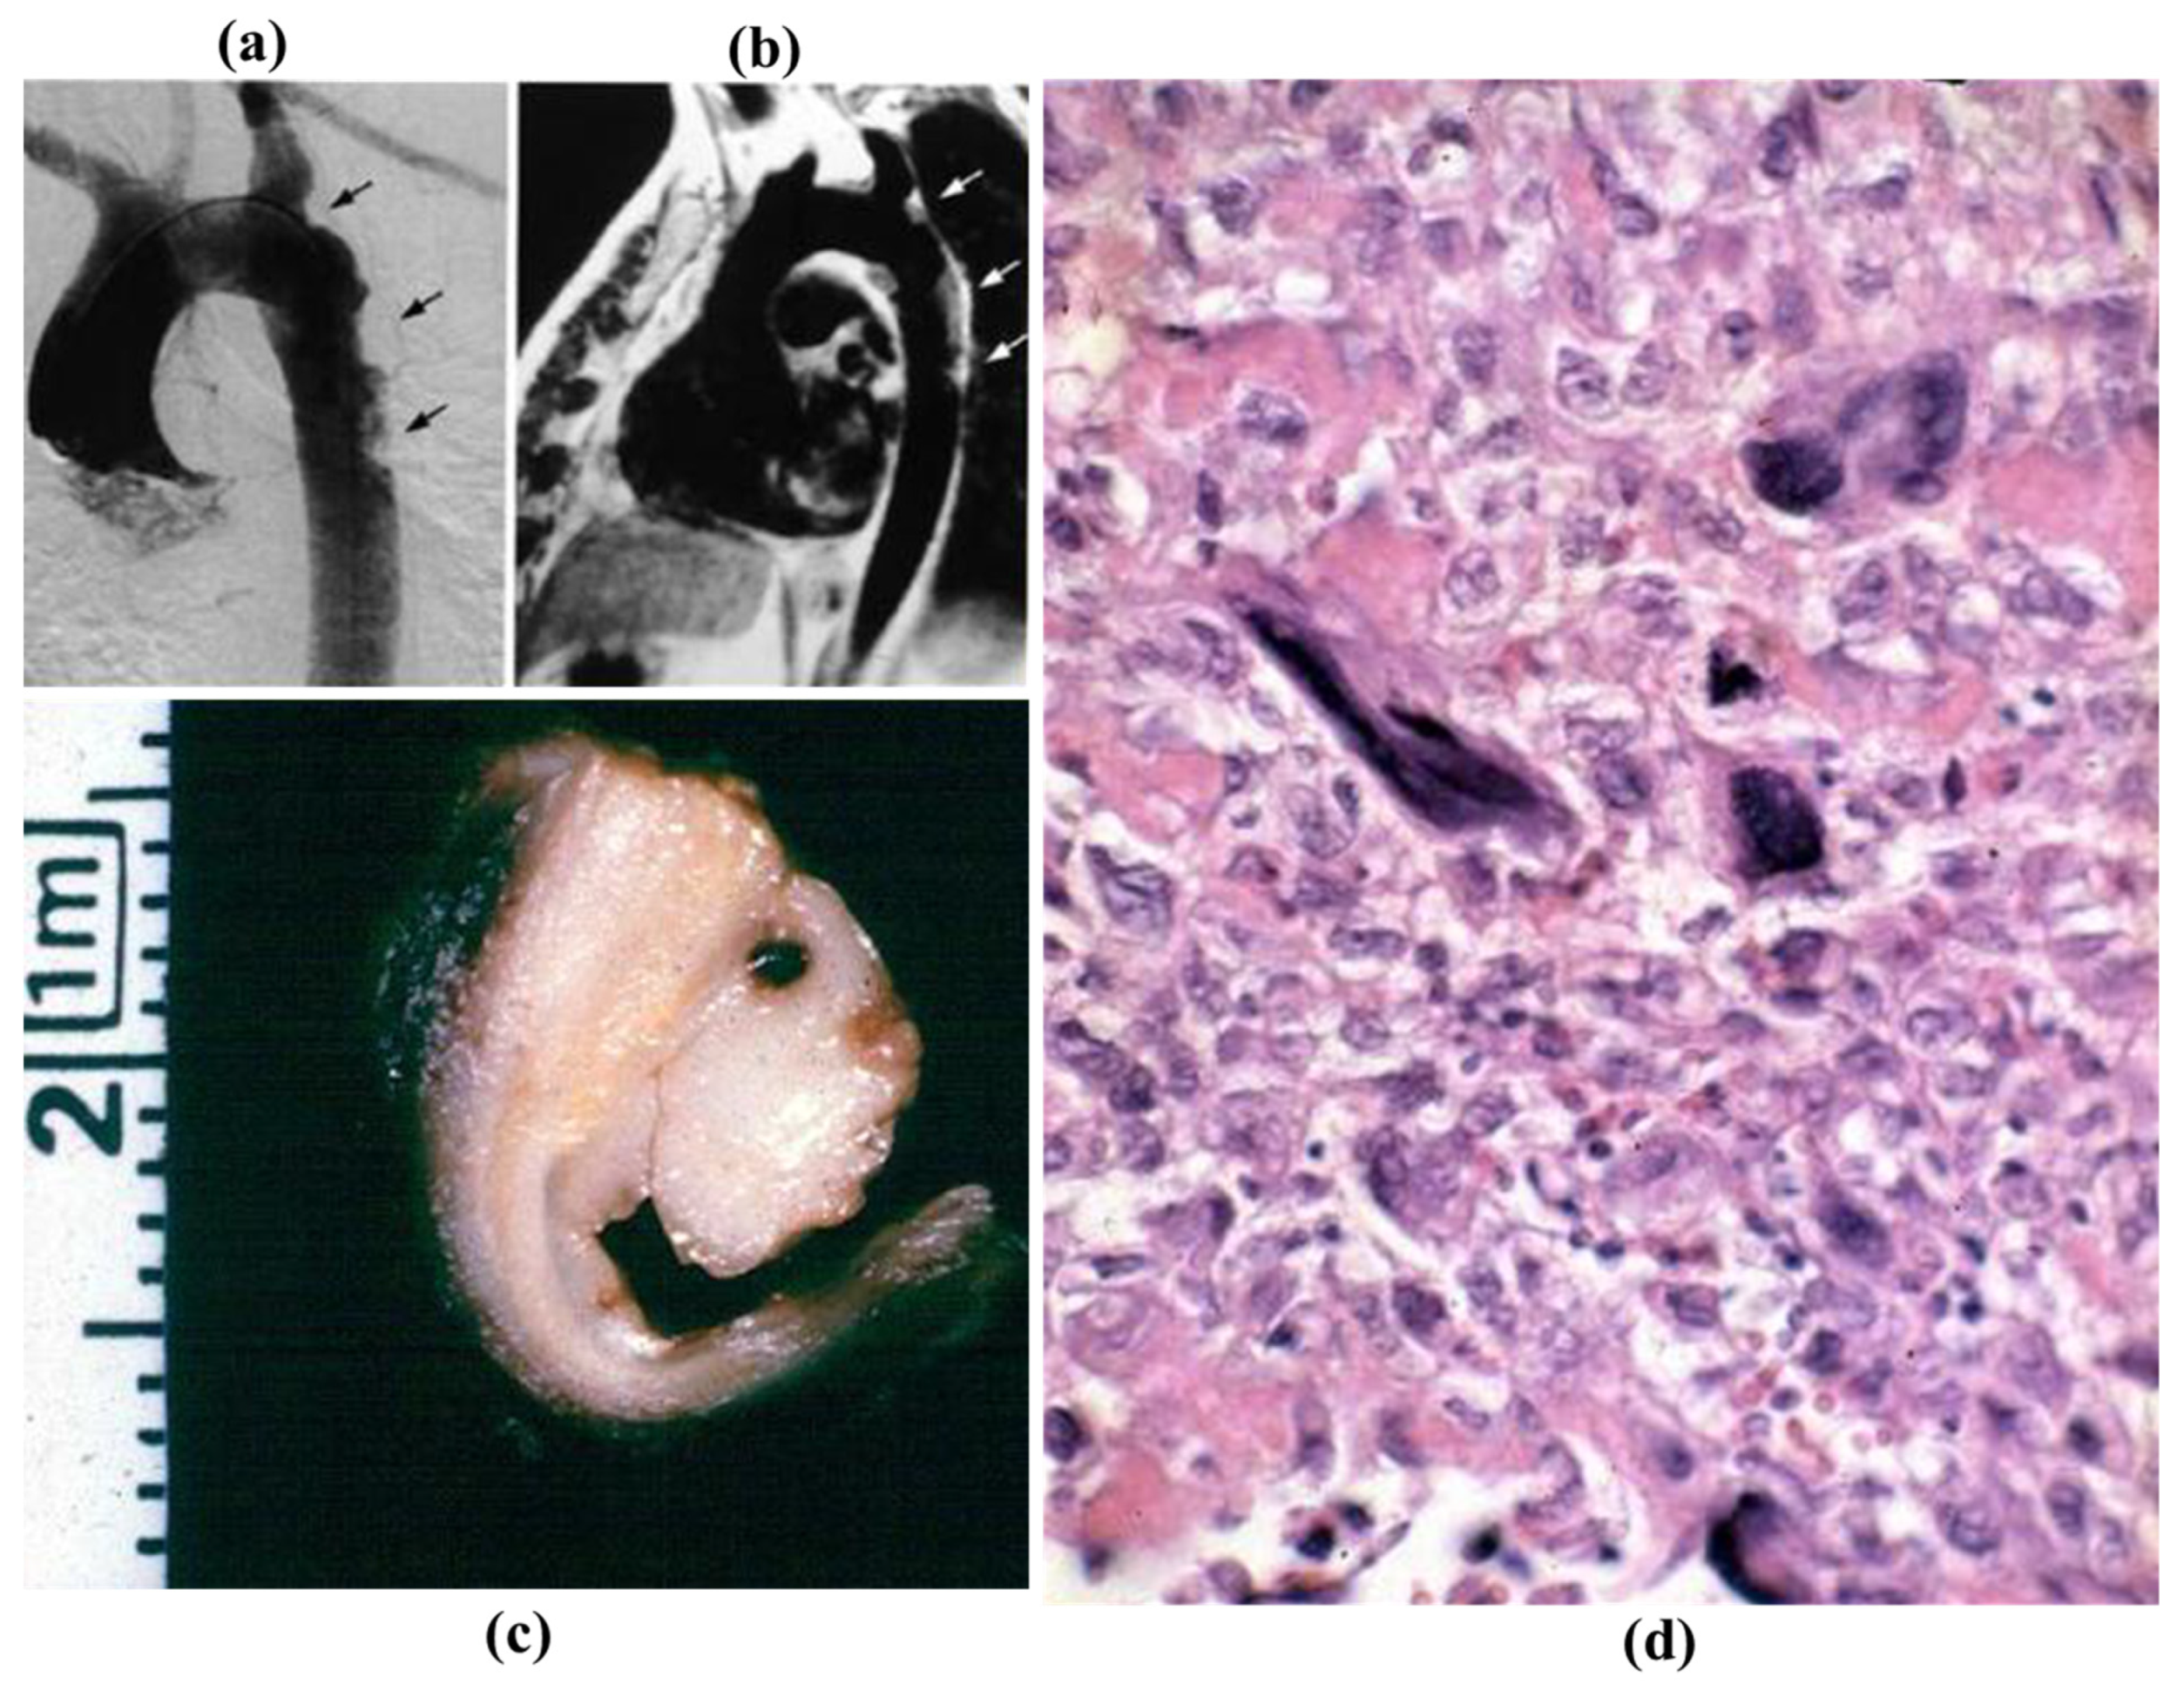

3.5. Neoplasms